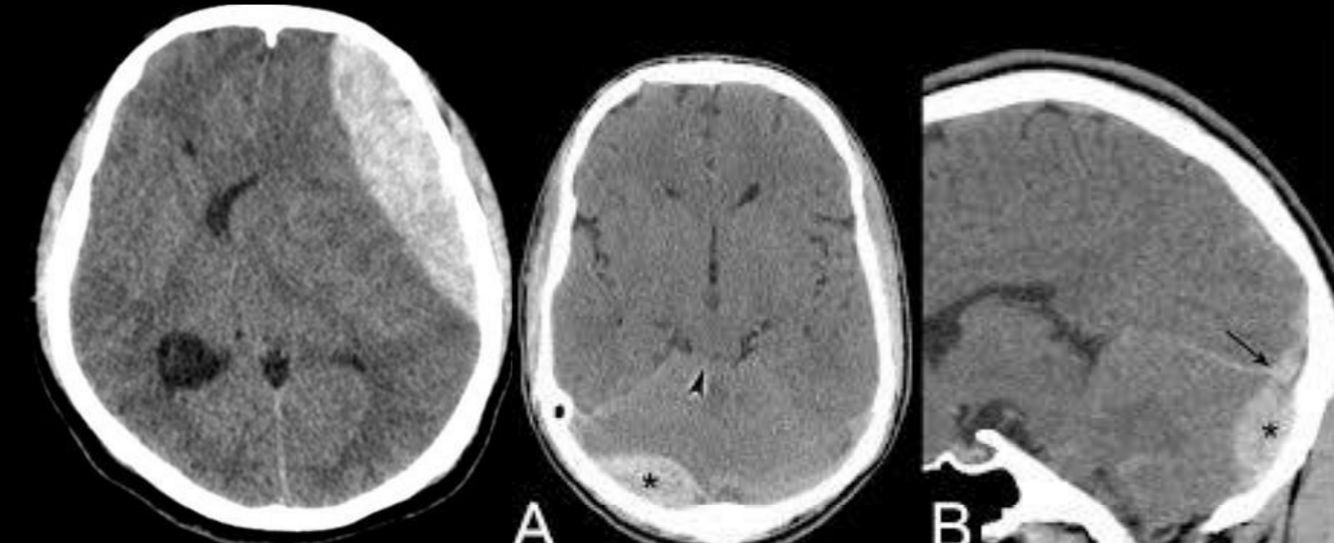

Hematoma subdural en TC

A

Colección semilunar / cóncava adyacente a superficie cerebral

venoso, lento

9

Q

Signo de subdural subagudo

Niveles sangre-líquido.

10

Hematoma epidural en TC

Colección biconvexa/lenticular, NO cruza suturas

arterial